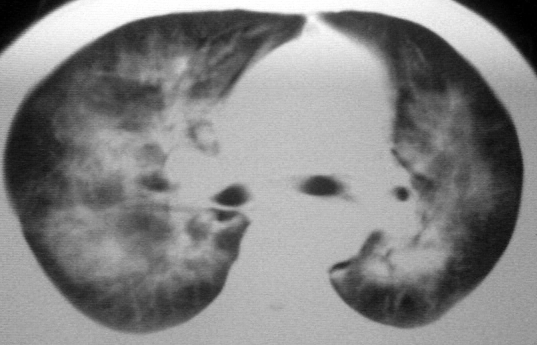

双肺内中部见略不对称性蝶翼状高密度区,边界不清,部分呈磨玻璃样密度,并可见含气支气管征。肺门、纵隔内未见肿大淋巴结影。无胸腔积液。

考虑:1、肺炎,建议进一步查冷凝集试验除外支原体肺炎;

2、不除外霉菌感染。

双肺炎性病灶.不除外霉菌及病毒感染

双肺斑片状密度均匀病灶,边界模糊可见充气支气管征,上野多于下野,不支持结核,1肺内感染,2查肾功,中心型肺水肿待除外.

同意肺炎诊断,至于病因,几乎可以除外结核,可以考虑病毒性、细菌性、霉菌性。

双肺中上野对称分布蝶翼样不均匀密度增高影,有支气管充气征,纵隔未见肿大淋巴结,发病突然,抗炎治疗无效,还是要考虑结核。

还是考虑肺水肿!蝶翼征.肺门增大,肺血管影增粗,!!病变累及中内带为主!要排外支原体感染.